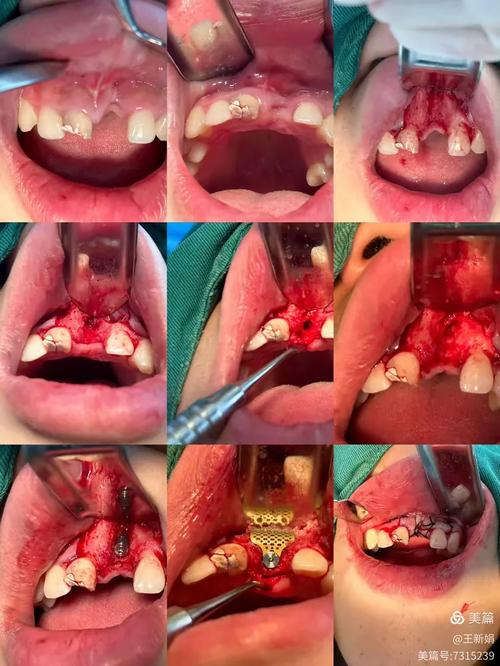

手术技术操作是植骨成功与否的核心环节,植骨量的设计需精准:骨量过少无法满足种植体植入需求,过多则可能因血供不足导致中央区域坏死;植骨区的处理至关重要,若牙槽骨表面软组织(如牙龈、肉芽组织)未彻底清除,会形成机械屏障,阻碍骨细胞附着;屏障膜的固定若不牢固,过早脱落或移位,会导致植骨材料流失,影响骨再生空间;种植体植入时机选择不当,如在植骨区未完全愈合时过早植入,可能干扰骨改建过程,导致种植体周围骨吸收。

面对植骨失败,需根据具体原因制定个体化处理方案,通过临床检查(探诊、叩诊)和影像学评估(CBCT、X光)明确失败类型:感染性失败需及时拆除松动的种植体(若已植入),彻底清创,刮除坏死组织,并细菌培养指导抗生素使用;骨量不足导致的失败,需重新评估骨缺损范围,可选择自体骨移植(如从颏部、髂骨取骨)以提高骨结合率;若植骨材料吸收过快,可考虑更换为生物相容性更好的材料,如脱矿冻干骨基质(DBM),术后需加强抗感染治疗,指导患者严格口腔卫生,并定期复查,待植骨区完全愈合(通常需3-6个月)后,再考虑重新种植。